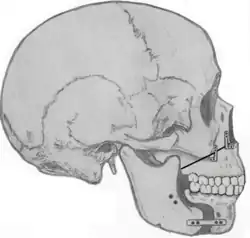

Tongue muscles (genioglossus, geniohyoid and others) are attached to the lower jaw below the teeth. During a genioglossus advancement procedure, the surgeon cuts a small window or bone cut in the front part of the lower jaw (mandible) at the level of the geniotubercle where the genioglossus muscle attaches. This piece of bone, along with the attachment for the tongue (genial tubercle) is pulled forward and subsequently secured to the lower jaw, usually with a single screw or with a plate and screws.